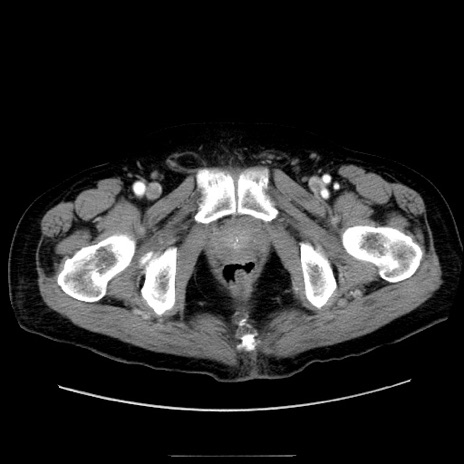

症例30(横断像)

【症例】80歳代男性

【現病歴】約6時間前から臍下部痛が出現。次第に腹部膨隆・背部痛も生じてきたため来院。背部痛の場所は変化しない。

【身体所見】意識清明、BT 36.3℃、BP  131/87mmHg、P 87bpm、SpO2 100%(RA)、臍周囲自発痛・圧痛あり、反跳痛なし、自発痛部位に一致して板状硬あり、腹部膨隆、腸雑音減弱、CVA tenderness両側陰性。

冠状断像